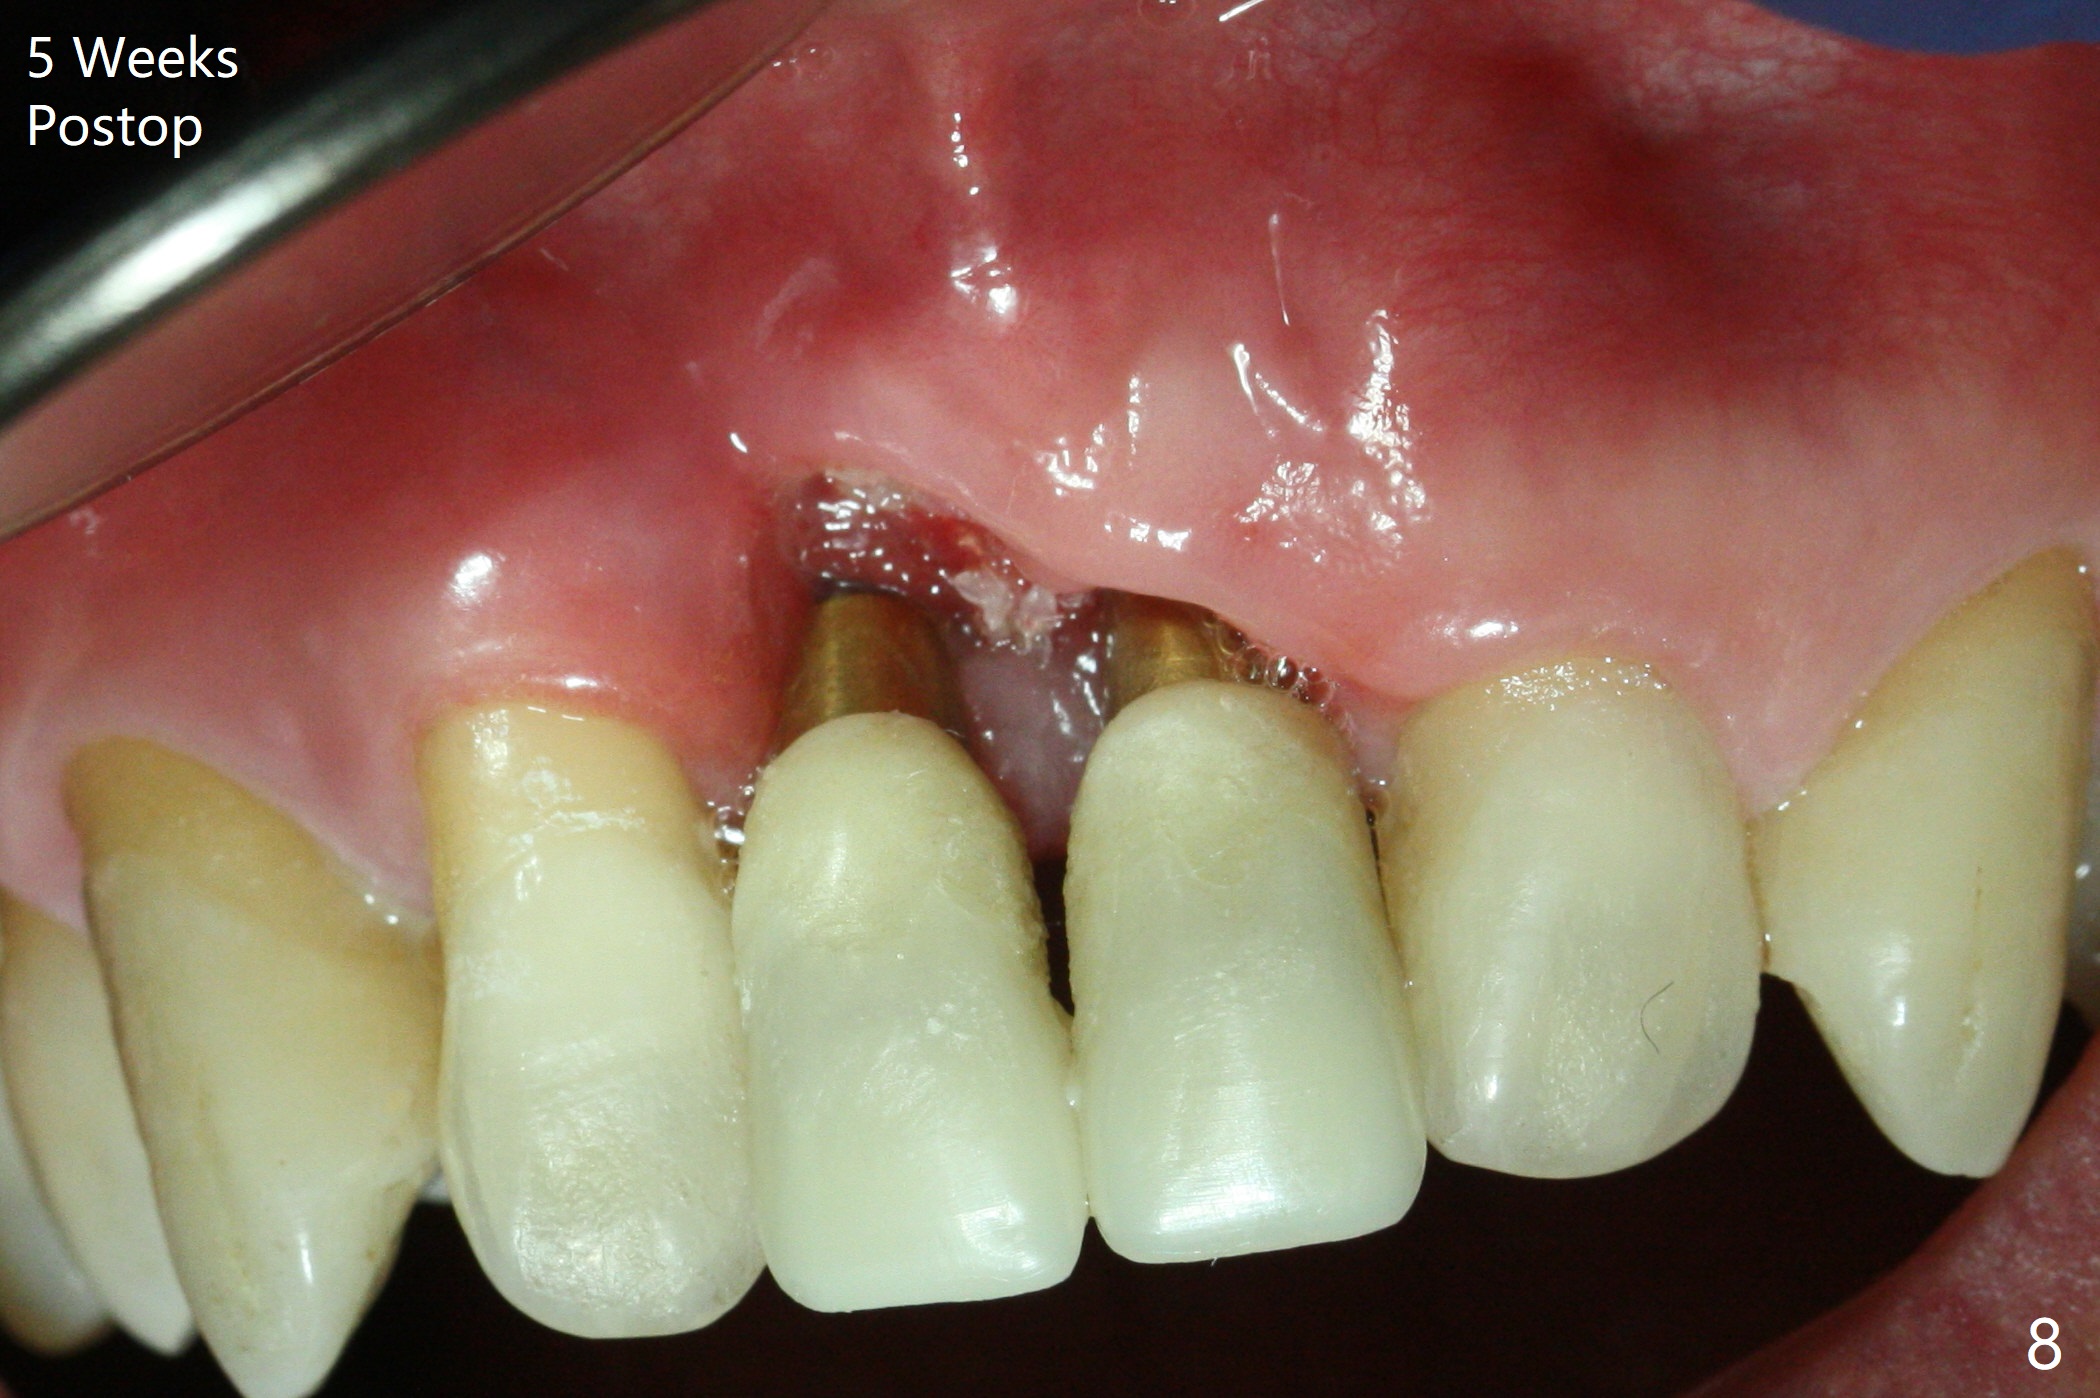

There is no buccal plate at #8 or 9 when the teeth are extracted as well as severe soft tissue defect at #8. Osteotomy is initiated as palatal as possible (Fig.1). When 3.5x13 mm implants are placed initially, the one at #8 is supracrestal (Fig.2 ^). To reduce the chance of peri-implantitis, the implant is placed deeper (Fig.3 (~2 mm implant threads exposed buccally)) with placement of sticky bone around the implants and 4.5x5.5(4) mm abutments (Fig.3 *). The buccal soft tissue defect #8 is repaired with a piece of PRF membrane (Fig.4 *), followed by periodontal dressing. Smaller 2-piece implants (3 mm, IBS) with smaller abutments (4 mm) may further reduce chance of periimplantitis and easy buccopalatal reduction of the abutments for restoration. The periodontal dressing remains stable 7 days postop (Fig.5) because it wraps around the abutments (Fig.6 A). By the time the periodontal dressing gets loose, #8 buccal soft tissue defect should be healing. When breaking-down periodontal dressing is removed 17 days postop, the coronal abutments and bone graft are exposed; after fabrication of provisional crowns (Fig.7), periodontal dressing is re-applied buccally. When the second dressing dislodges 5 weeks postop, the buccal soft tissue appears to reduce (Fig.8). Raising flaps may be less traumatic. A piece of bone graft is being extruded 4 months postop (Fig.9 >). After the abutments change from 4.5x5.5(4) to 4.5x7(3) mm, new temporary crowns are fabricated (Fig.10 (4.5 months postop)). CT shows apparent buccal bone at #8 and 9 (Fig.11,12). How to improve cosmetic?